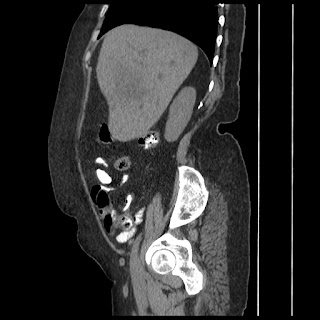

A 70 years old woman with Obstractive jaundice & palpable GB